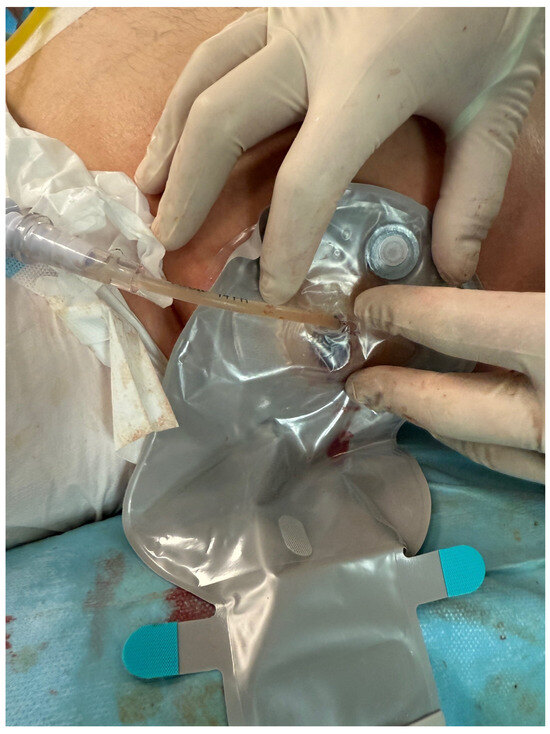

The PEN procedure was performed under general anesthesia with endotracheal intubation in the supine position. Percutaneous endoscopic necrosectomy was performed under the guidance of ultrasound (using a Logiq P9, convex C1-6 MHz probe) and fluoroscopy. Following the establishment of percutaneous drainage, Cook Medical Acrobat 2 AWG2-35-45 guidewire was inserted and looped inside the lumen of the necrotic collection (Figure 1 and Figure 2) to be followed by implantation of a fully coated self-expandable Evolution® esophageal controlled-release stent 120 mm or 150 mm in length and 20 mm in diameter (Figure 3 and Figure 4). A flexible Evis Exera III CF-H190L endoscope–gastroscope (Olympus) was then inserted into the necrotic collection through the lumen of the esophageal stent, and a percutaneous endoscopic necrosectomy procedure involving mechanical removal of necrotic tissue from the collection under direct endoscopic image guidance was performed (Figure 5, Figure 6 and Figure 7). A Dormia basket (Figure 8) was used to remove necrotic tissue. In the course of the percutaneous endoscopic necrosectomy procedure, the necrotic collection was extensively flushed with physiological saline, and the contents from the reservoir were aspirated. The PEN procedure was considered complete upon removal of demarcated necrotic tissues or upon bleeding from the inflammatory granulation tissue within the necrotic collection. If subsequent percutaneous endoscopic necrosectomy procedures were required in the same patient, the esophageal stent was left in the percutaneous position, and one or two 16 Fr silicone drains (depending on the size of the collection) were inserted into the lumen of the necrotic collection through the stent to maintain patency. The drain(s) were used to flush the collection with 100 mL of physiological saline 6 times a day. Following the completion of endoscopic treatment using percutaneous access, the esophageal stent was removed, and the stenting site was secured with a stoma bag to drain the remaining contents from the residual necrotic collection (Figure 9).

Figure 9. Completed percutaneous endoscopic necrosectomy, with a drainage bag applied at the site of the self-expandable stent. Source: Department of General, Gastroenterological, and Oncological Surgery, L. Rydygier Regional Hospital in Toruń.